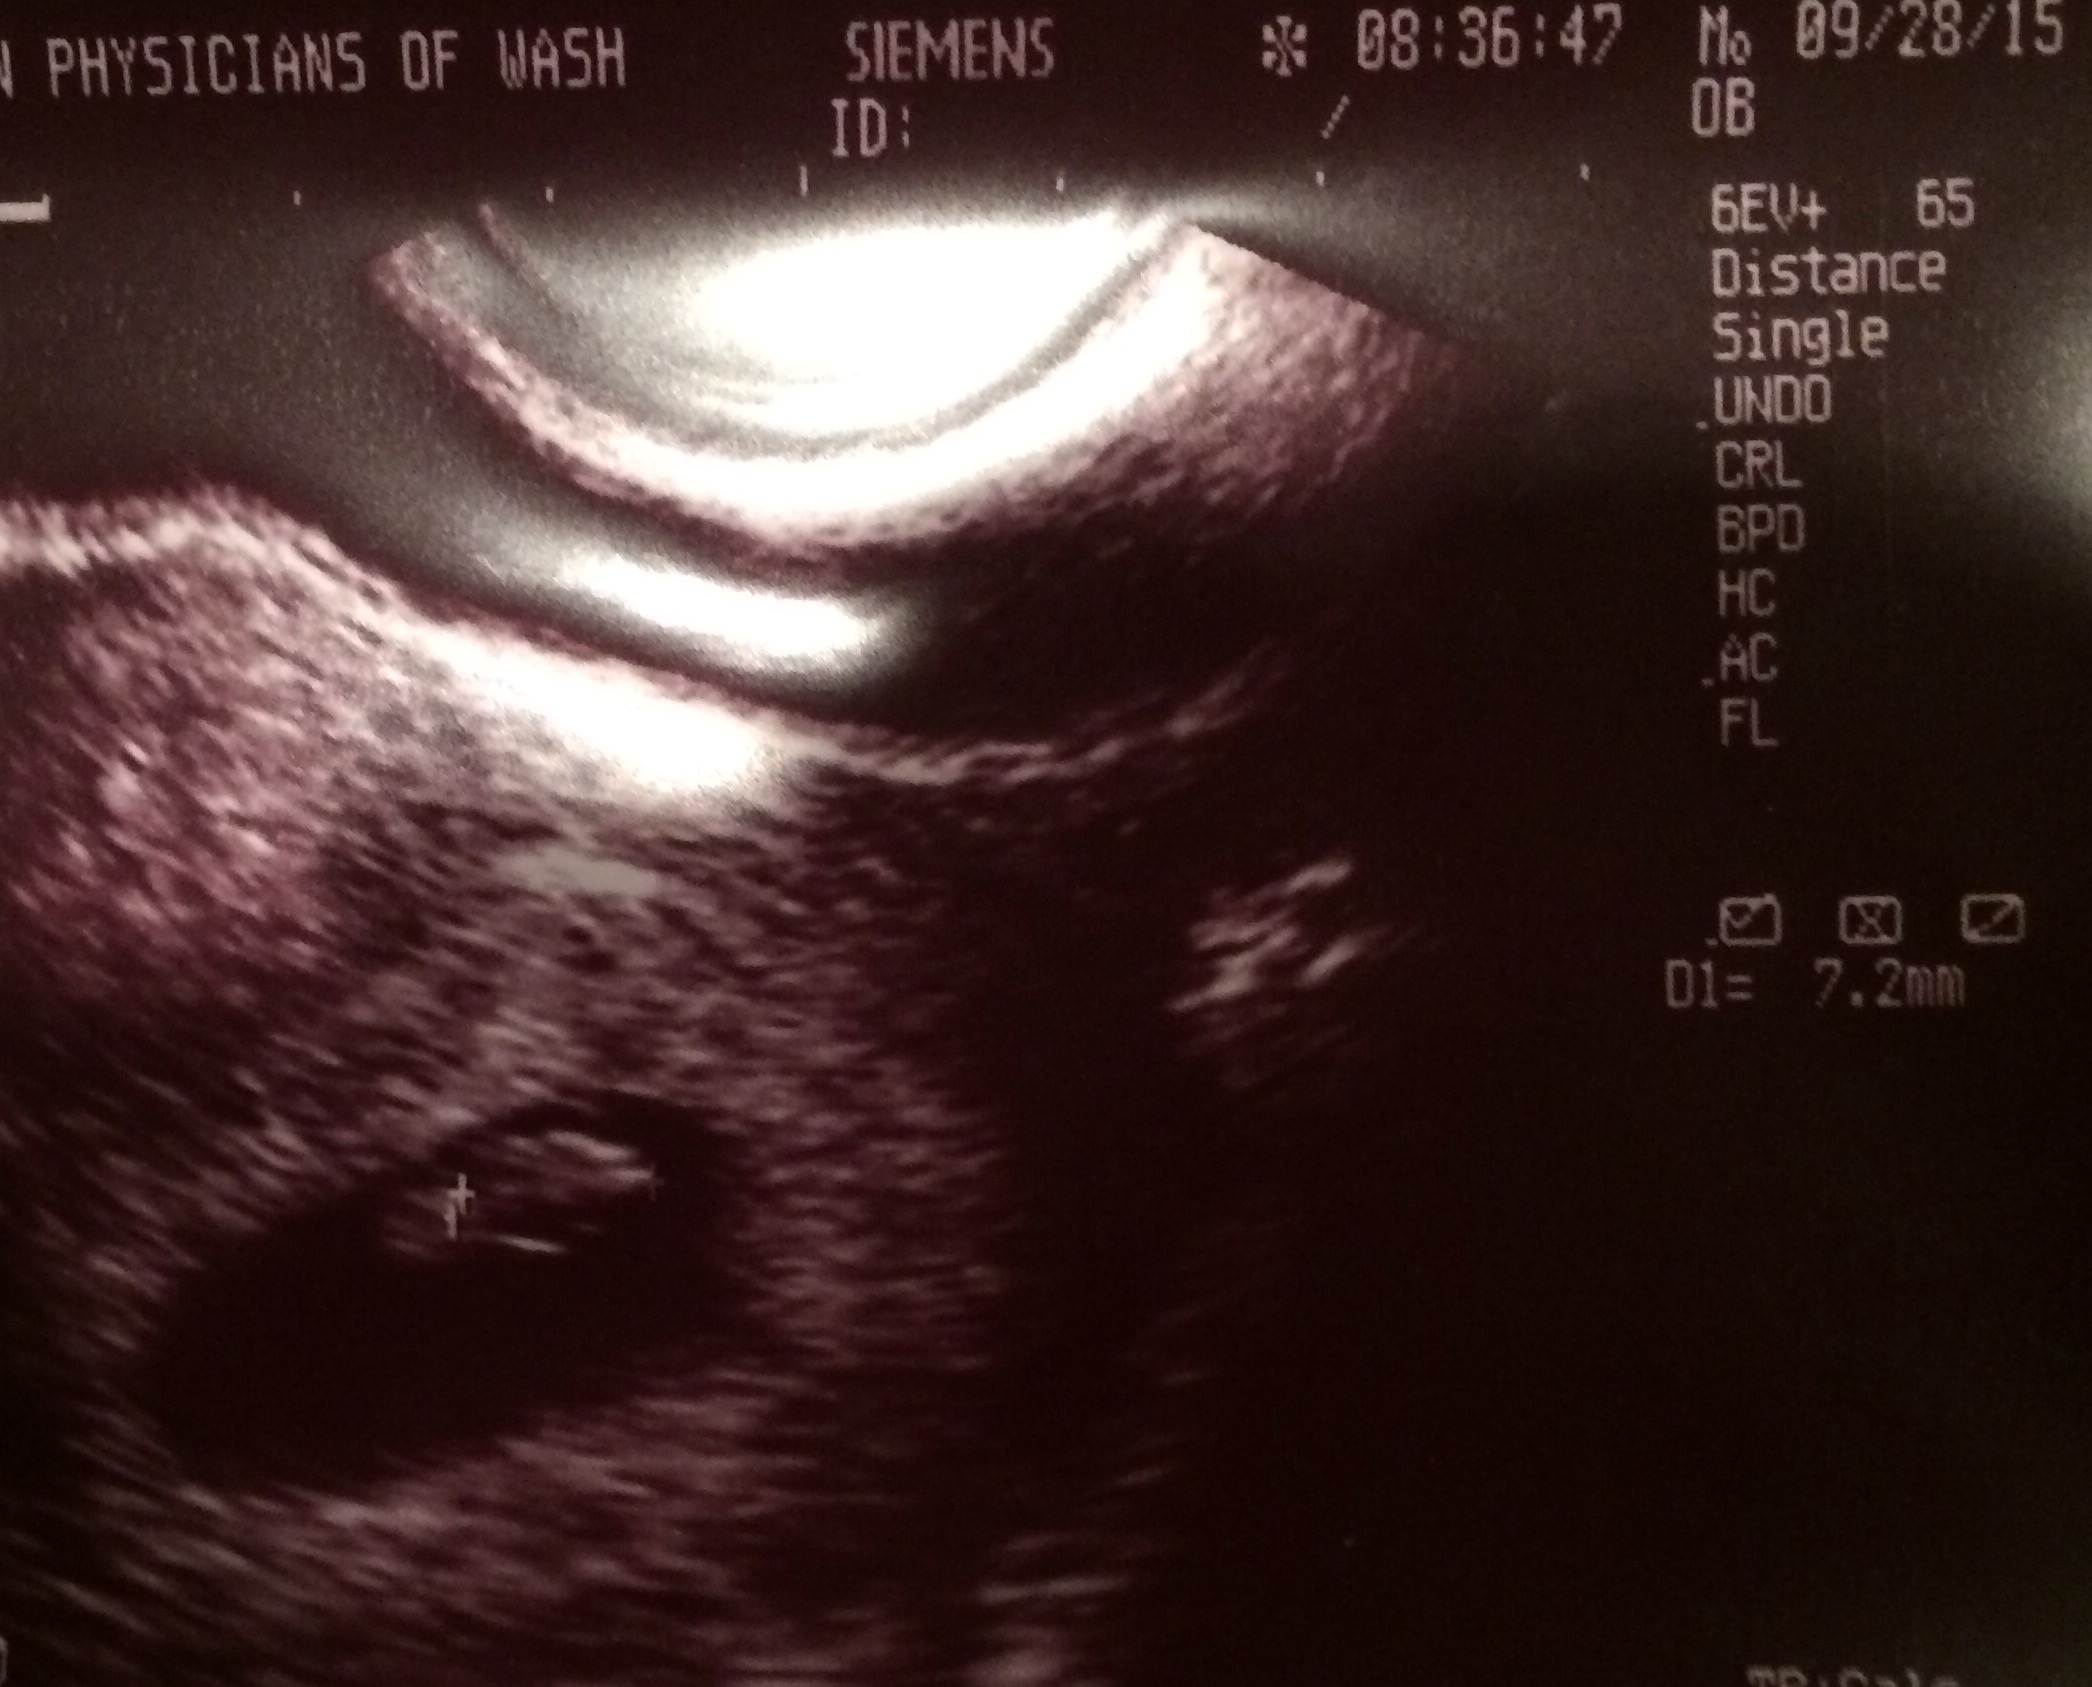

Measuring 2 days ahead of where we thought we were! Heart beat 120 bpm! What an amazing sound! Tears for this emotional momma!! I'm tearing up now even!

Slight bleeding in the top right of the photo that we are watching, but my doc says it's fairly common and should go away.

Due date May 15! Two days before my husband's birthday!